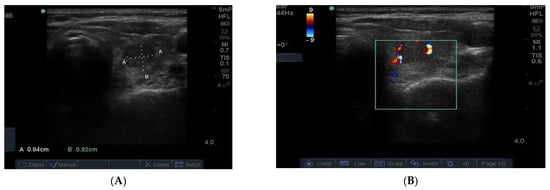

The blood supply to thyroid nodules is an important feature to be documented in the course of real time ultrasonography. There are three types of vascularity to be discussed. Firstly, the so-called hypoechoic halo surrounding a benign nodule is caused by compressed blood vessels which can be seen when the “colour” button is engaged. An example of this is seen in Figure 9A. Secondly, the degree of vascularity around the outside of a nodule is reflective of its activity and prominent blood supply around a nodule maybe a sign of thyroid cancer (Figure 9B) [] but can also be present around nodules shown by biopsy to be benign. It has recently been shown that blood vessels within a nodule, especially if it has other suspicious features (Figure 9B), may be a reliable sign of cancer [].

Figure 9.

Examples of vascularity around the edge of a benign nodule and (A) associated with blotchy macrocalcifications in a hard, irregular edged nodule that is suspicious for papillary cancer (B). Another example of macrocalcifications in papillary thyroid cancer.

In Figure 10 is shown matching images of a benign nodule without (A) and with (B) blood flow in the halo around the nodule.

Figure 10.

A small 8 mm benign nodule in the left thyroid lobe shown as an ultrasound image (A) and with surrounding vascularity in (B).